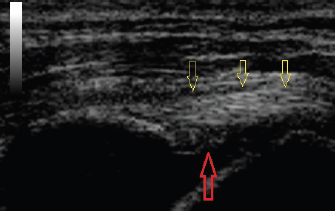

Fig. 1. Longitudinal ultrasound image of an acutely torn biceps tendon (yellow arrows). The tear itself can be seen as an absence of fibers between the two “+” symbols.

Fig. 2. The same biceps tendon as Figure 1 (yellow arrows) 8 weeks following intralesional injection with bone marrow aspirate concentrate and platelet-rich plasma. Significant fiber infilling of the previous lesion can be seen.